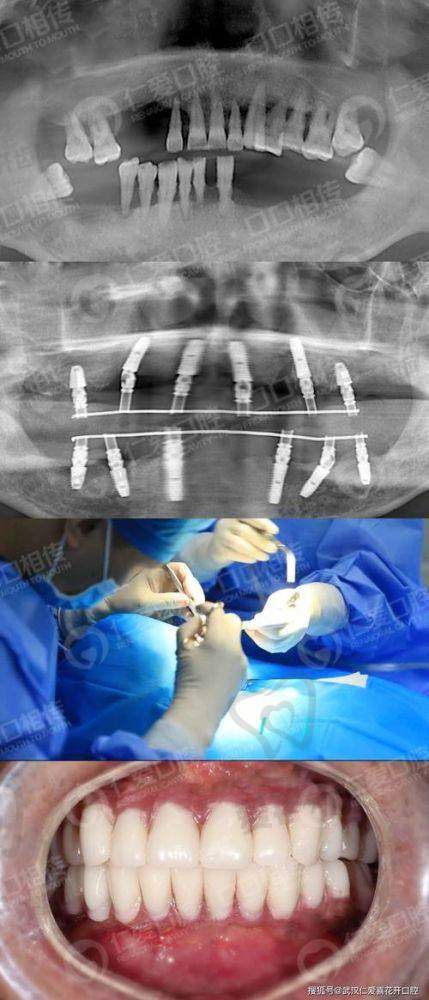

全口牙种植的过程是怎样的?

术前检查和评估:患者首先需要到医院进行全方面的口腔检查,包括口腔X光片、CT扫描等,了解口腔内部的情况,如牙槽骨的密度、高度、宽度等。医生会根据检查结果评估患者是否适合进行全口牙种植手术,并制定个性化的种植方案。

种植体植入手术:在局部麻醉下,医生会在患者的牙槽骨上制备种植窝,然后将种植体植入其中。手术过程中患者一般不会感到明显的疼痛,但术后可能会有轻微的肿胀和疼痛,这是正常的反应,通常会在几天内逐渐缓解。

愈合期:种植体植入后,需要等待一段时间让种植体与牙槽骨形成骨结合,这个过程一般需要3 - 6个月。在愈合期间,患者需要遵循医生的建议,注意口腔卫生,避免食用实力强的食物。

安装牙冠:当种植体与牙槽骨完全结合后,医生会为患者安装牙冠。牙冠的安装过程相对简单,安装完成后,患者就可以正常使用种植牙齿了。